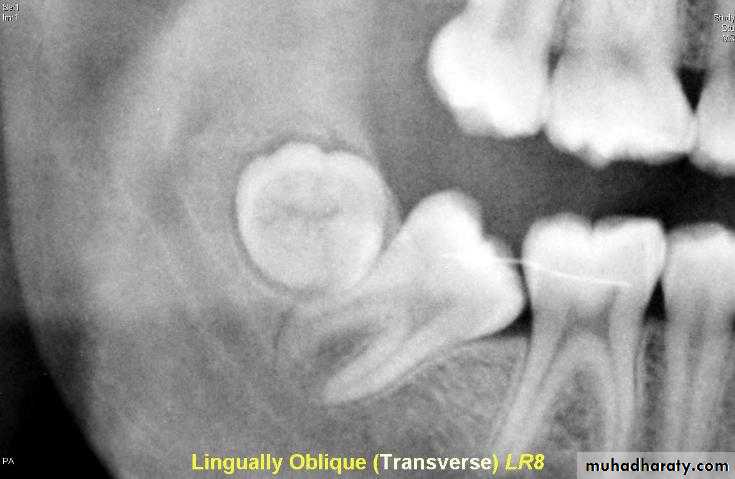

a –the tube shift techniqueUses two periapical radiographs, shifting the tube horizontally between exposures.

If the unerupted teeth moves in the same direction in which the tube is shifted, its located on the lingual or palatal side

A facial or buccally located tooth moves in the opposite direction to the tube shift.

b – periapical and occlusal film

Uses the periapical radiograph taken with standard technique and an occlusal radiograph to give different views of the impacted tooth